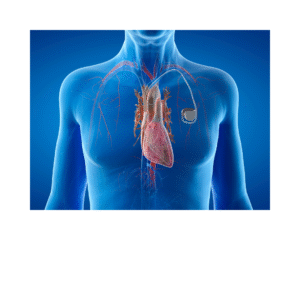

Vamos falar sobre Marcapasso?

Marcapasso aliado do coração! O que é um marcapasso? Um marcapasso é um pequeno dispositivo eletrônico que é implantado sob a pele, geralmente perto da

Marcapasso aliado do coração! O que é um marcapasso? Um marcapasso é um pequeno dispositivo eletrônico que é implantado sob a pele, geralmente perto da